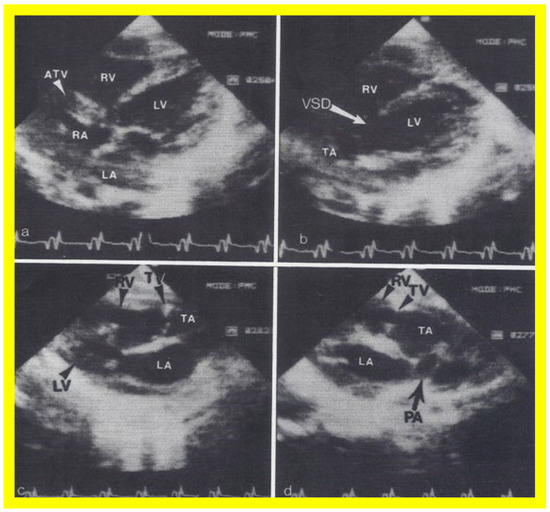

Figure 13. Two dimensional echocardiographic video frames demonstrating (a) an atretic tricuspid valve (ATV) between the right atrium (RA) and right ventricle (RV), (b) a large subtruncal ventricular septal defect (VSD), (c) thickened and somewhat domed truncal valve (TV) leaflets, and (d) the origin of the pulmonary artery (PA) from the posterior aspect of the truncus arteriosus (TA). LA, left atrium; LV, left ventricle. Reproduced from Rao PS, et al. Am Heart J 1991;122:829–835 [31].

Applsci 11 09472 g013

Figure 14. Video frames from a two dimensional echocardiographic and color Doppler study demonstrating (a) an atretic tricuspid valve (ATV) between the right atrium (RA) and right ventricle (RV), and blood flow from the left atrium (LA) into the left ventricle (LV) across the mitral valve. The RV (arrow) is very small and hypoplastic. (b) LV and RV with a large ventricular septal defect (VSD) below the truncus arteriosus (TA). Turbulent flow across the truncal valve suggests truncal valve stenosis. (c) The origin of the pulmonary artery (PA) from the TA by color flow (arrow), and (d) the division into right (RPA) and left (LPA) pulmonary arteries from the PA in a short-axis view. TV, truncal valve leaflets. Reproduced from Rao PS, et al. Am Heart J 1991;122:829–835 [31].

The relationship of the great arteries is examined next in order to classify them into various types, as mentioned above. The relationship of the great arteries (Figure 2, top) is established by following the vessels arising from the ventricles until the pulmonary artery (PA) bifurcation or aortic arch. In Type I patients with normally related great arteries, the aorta arises from the LV (Figure 10) and in Type II patients with transposition of the great arteries, the PA arises from the LV (Figure 11; Figure 12). In Type II patients, the blood vessel arising from the LV should be traced to demonstrate its branching into the right and left PAs (Figure 11; Figure 12). In Type III patients, it may be a little more difficult to assign the great artery relationship and, sometimes, other imaging studies, including angiography, may be needed to define the great artery relationship. In Type IV with truncus arteriosus, the limited data suggest that this can be performed by echocardiography (Figure 13; Figure 15). In the example shown [31], the atretic tricuspid valve (Figure 13a and Figure 14a), VSD (Figure 13b and Figure 14b), hypoplastic RV (Figure 14a), single vessel (truncus) arising from the heart (Figure 13c,d, and Figure 14c,d), and origin of the PA and its division into branch PAs (Figure 13d, and Figure 14c,d) were demonstrated.